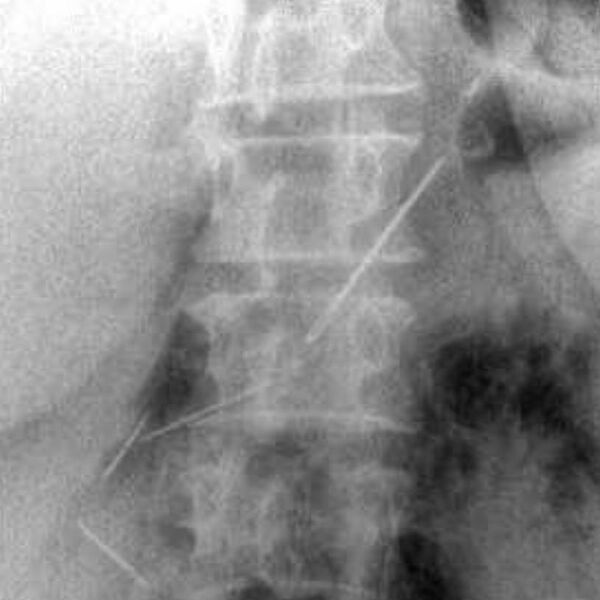

Пожилая женщина обратилась в Красногорскую больницу с жалобами на боли в животе. Пациентку обследовали и выяснили, что у нее в брюшной полости и одной передней брюшной стенке находятся четыре иглы.

Выяснилось, что женщина проглотила их около месяца назад — при каких обстоятельствах это случилось, не уточняется. За время нахождения в организме иглы успели обрасти тканями.

Медики провели пациентке лапаротомию и удалили все инородные предметы. Одна из игл проникла в поджелудочную железу, но орган все же удалось сохранить. Вмешательство прошло успешно.